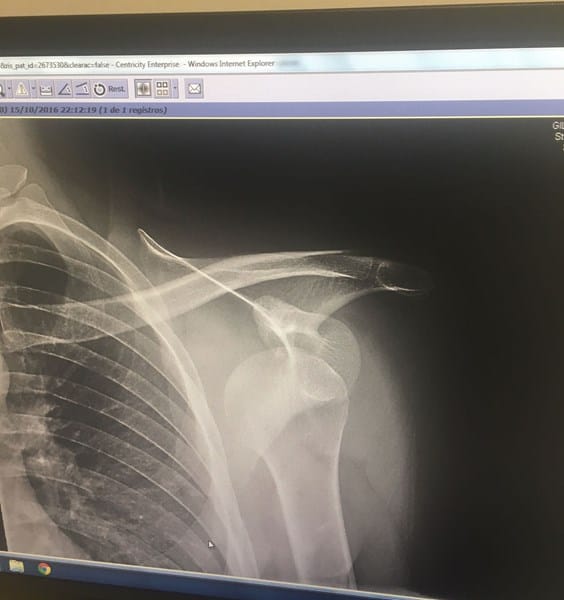

El día 15 de octubre de 2016 sufrí una caída en el trabajo y como consecuencia sufrí una luxación anterior del hombro izquierdo. (Os dejo foto de la placa)

"Importante engrosamiento, con edema, y desestructuración, que afecta al labrum glenoideo anteroinferior, anterior y posteroinferior, que sugiere probable lesión de su base implantación (lesión de Bankart). Confirmar con artrorresonancia.

Importante erosión en la cortical postero la cabeza humeral, con edema óseo asociado que sugiere lesión de Hill-Sachs aguda.